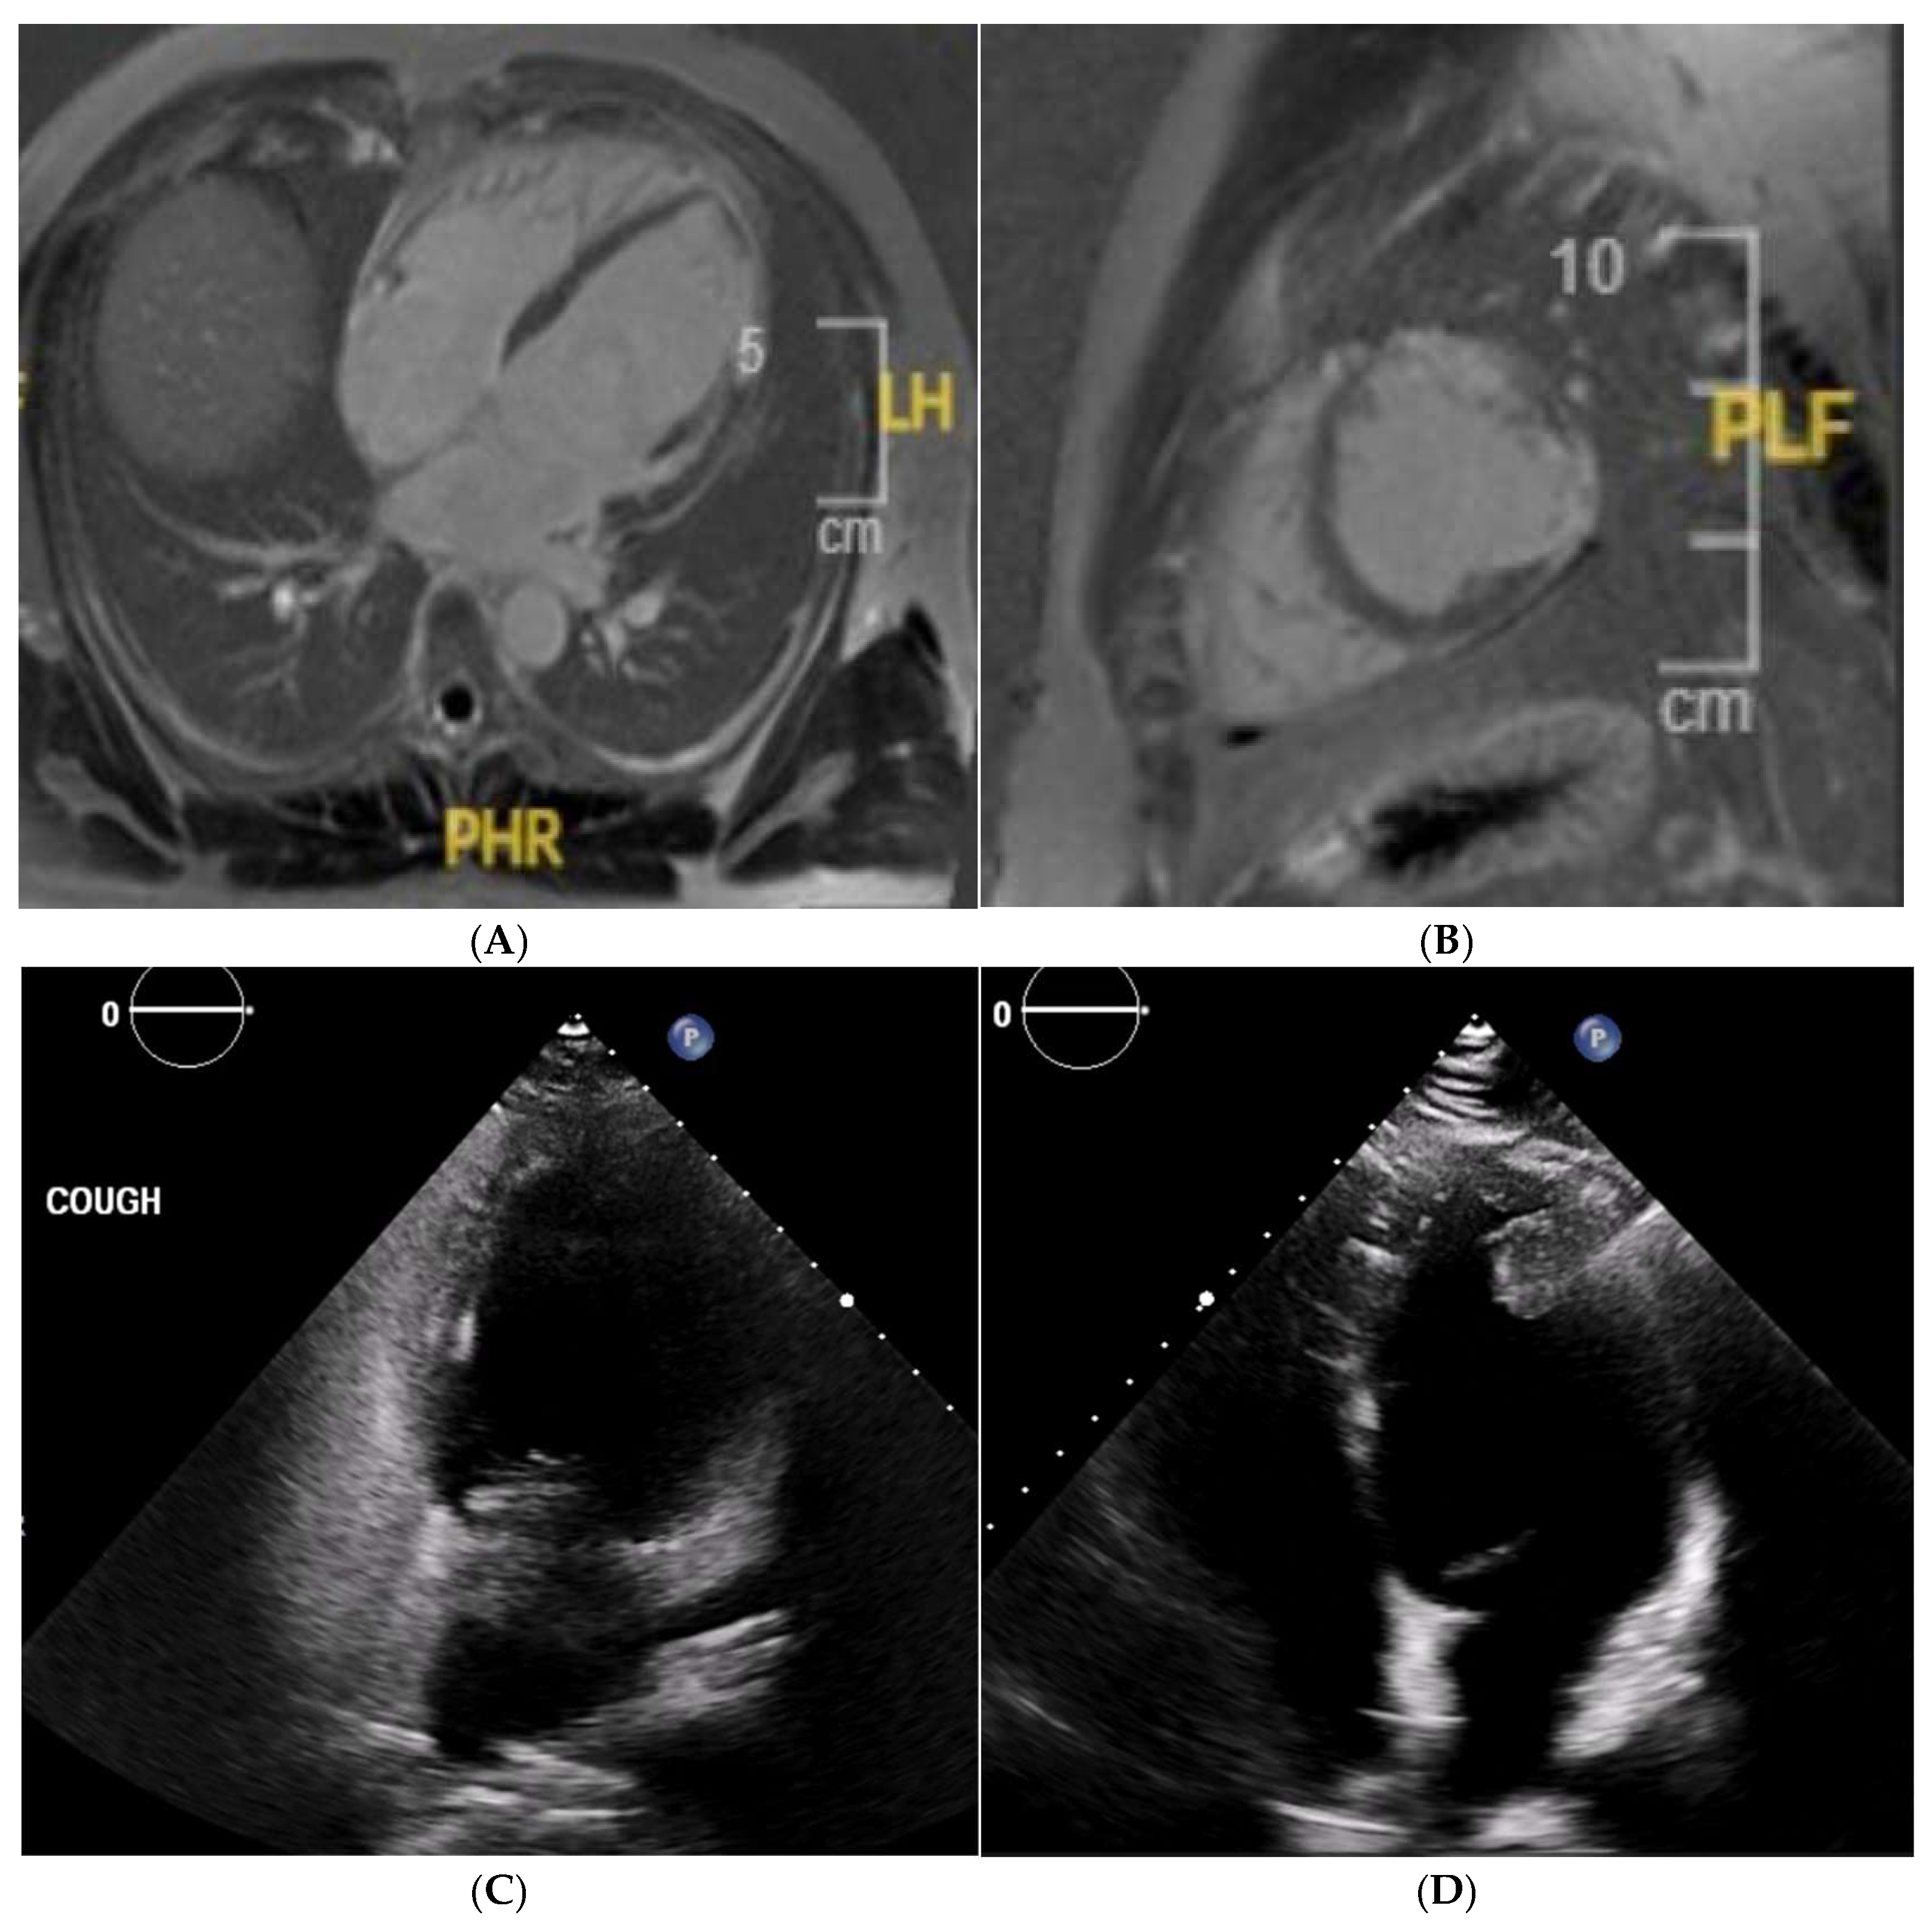

10. Arrhythmogenic Right Ventricular Cardiomyopathy